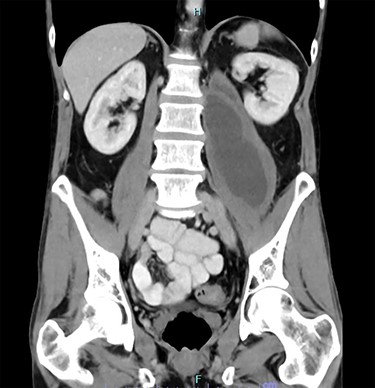

A 45-year-old man presented to his general practitioner complaining of 2 months of progressive left hip pain. Over the preceding 2 weeks he had been struggling to mobilize. His general practitioner (GP) investigated with a non-contrast computed tomography (CT) of the pelvis. This found a cystic lesion within the left psoas muscle with areas containing coarse calcification. The findings, overall, were suspicious of tumour, likely a teratoma. A CT chest, abdomen and pelvis with intravenous contrast was arranged. The pathology in the left psoas was found to represent a pancreatic pseudocyst extending from a heavily calcified pancreas, over the anterior aspects of the aorta and inferior vena cava (IVC) before reaching the left psoas muscle body (Figs 1 and 2). There were multiple other cystic regions noted within the pancreatic parenchyma and peripancreatic tissue. The patient was referred to the emergency department for surgical review.

CT showing calcified pancreas with pseudocyst extending from pancreas to left psoas muscle.